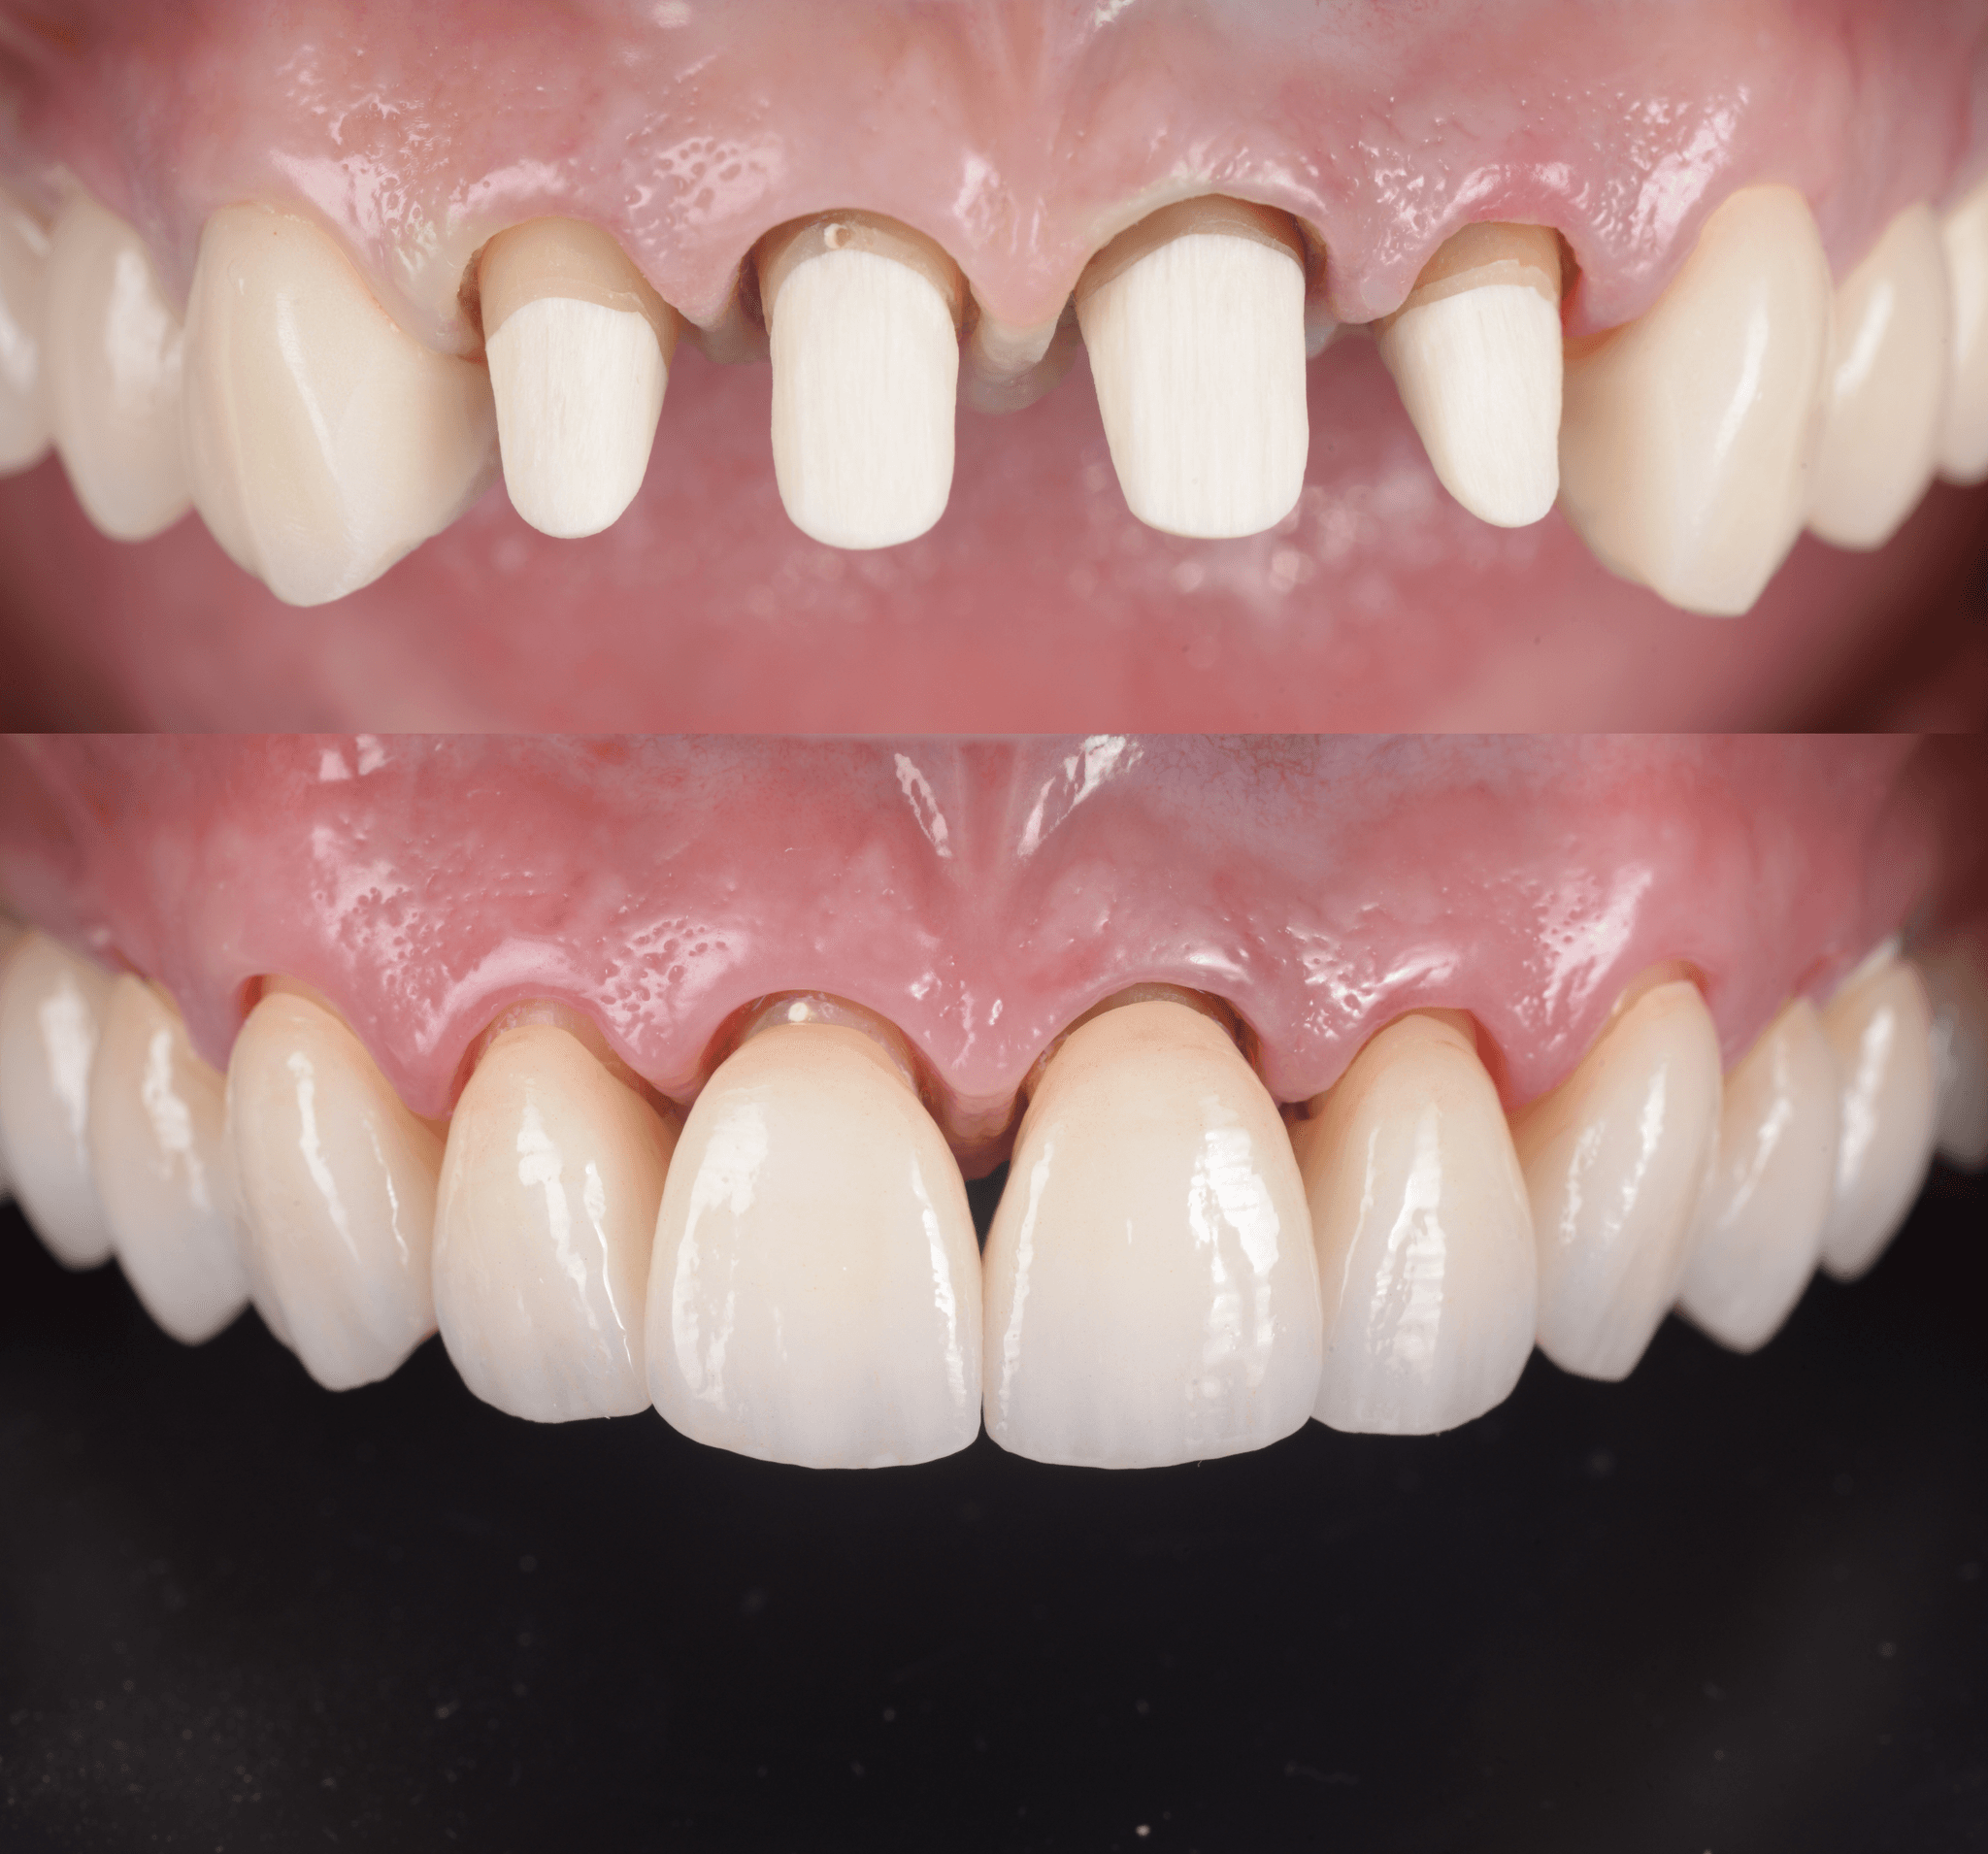

După ce canalele sunt obturate, evaluăm tipul de restaurare potrivit. În multe cazuri, mai ales când dintele păstrează suficientă structură, o restaurare directă din compozit este suficientă. Pentru dinții sever compromiși, putem folosi un pivot și bont intern proiectat CAD înainte de aplicarea unei coroane.

Succesul endodontic nu se măsoară doar prin ceea ce este îndepărtat, ci prin modul în care dintele funcționează ulterior. Planificăm restaurarea încă de la început, asigurându-ne că dintele poate funcționa corect și poate susține lucrări protetice viitoare, dacă este necesar.

Când reconstrucția structurală este necesară, nu folosim pivoți standard. Folosim pivoți personalizați, proiectați digital pe baza scanării dintelui tău, pentru o potrivire optimă și o distribuție corectă a forțelor. Această abordare îmbunătățește retenția, reduce riscul de fractură și se aliniază cu planul protetic final.